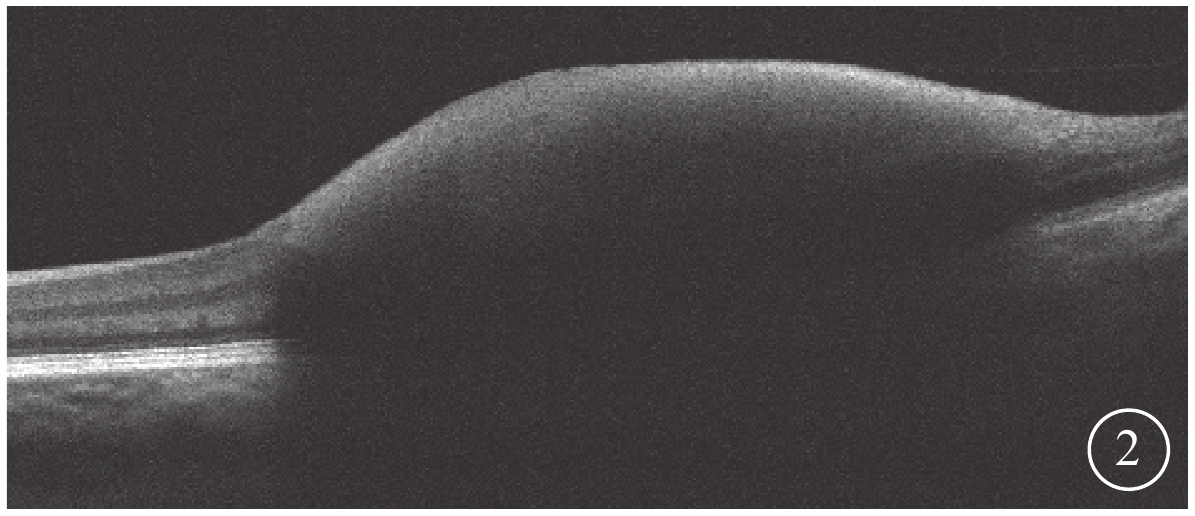

3只眼均行常規全身檢查及最佳矯正視力(BCVA)、眼壓、裂隙燈顯微鏡、眼底彩色照相、眼部B型超聲、熒光素眼底血管造影(FFA)及光相干斷層掃描(OCT)等眼部檢查。患眼BCVA為手動/20 cm~0.06,平均BCVA為0.03±0.02。眼壓為7.9~18.9 mmHg(1 mmHg=0.133 kPa),平均眼壓為(9.87±3.23)mmHg。3只眼均存在不同程度的晶狀體混濁。RAM位于視網膜顳上2只眼,位于視網膜顳下1只眼。黃斑區內界膜下出血大小為1.5~8.0倍視盤面積。FFA檢查發現,動脈期患眼顳下視網膜動脈分支處強熒光點,周圍出血遮蔽視網膜及脈絡膜熒光(圖1)。OCT檢查發現,患眼出血灶表面可見一弧形強反射條帶,且與內界膜相對應,其下呈點狀強反射(圖2)。

圖2

圖1同眼OCT像。黃斑視網膜內層強反射

圖2

圖1同眼OCT像。黃斑視網膜內層強反射

3只患眼經FFA檢查均可見動脈期顳側視網膜動脈分支處強熒光點,周圍出血遮蔽視網膜及脈絡膜熒光;OCT檢查可見出血灶表面一弧形強反射條帶,且與內界膜相對應,其下呈點狀強反射。證明其RAM及內界膜下出血診斷成立[5]。

3只眼均行常規全身檢查及最佳矯正視力(BCVA)、眼壓、裂隙燈顯微鏡、眼底彩色照相、眼部B型超聲、熒光素眼底血管造影(FFA)及光相干斷層掃描(OCT)等眼部檢查。患眼BCVA為手動/20 cm~0.06,平均BCVA為0.03±0.02。眼壓為7.9~18.9 mmHg(1 mmHg=0.133 kPa),平均眼壓為(9.87±3.23)mmHg。3只眼均存在不同程度的晶狀體混濁。RAM位于視網膜顳上2只眼,位于視網膜顳下1只眼。黃斑區內界膜下出血大小為1.5~8.0倍視盤面積。FFA檢查發現,動脈期患眼顳下視網膜動脈分支處強熒光點,周圍出血遮蔽視網膜及脈絡膜熒光(圖1)。OCT檢查發現,患眼出血灶表面可見一弧形強反射條帶,且與內界膜相對應,其下呈點狀強反射(圖2)。

圖2

圖1同眼OCT像。黃斑視網膜內層強反射

圖2

圖1同眼OCT像。黃斑視網膜內層強反射

3只患眼經FFA檢查均可見動脈期顳側視網膜動脈分支處強熒光點,周圍出血遮蔽視網膜及脈絡膜熒光;OCT檢查可見出血灶表面一弧形強反射條帶,且與內界膜相對應,其下呈點狀強反射。證明其RAM及內界膜下出血診斷成立[5]。